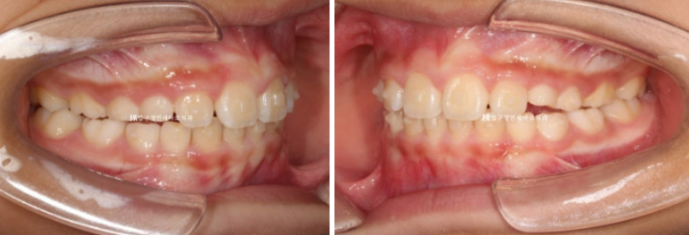

23.04

가장 먼저 보이는 것은 앞니 사이가 벌어진 것 이지만

이 벌어짐은 송곳니가 나오면서 모이기도 하기 때문에 큰 문제는 아닙니다.

그보다는 윗니가 아랫니를 많이 덮어 아랫니가 잘 보이지 않습니다.

과개교합 이라고 합니다.

윗니 아랫니 중심선이 맞지 않는 중심선 불일치도 보입니다.

옆에서 보시면 윗니 돌출이 심해보입니다.

하지만 골격 분석을 해보면 아래턱이 작아서 그렇게 보이는 것 입니다.